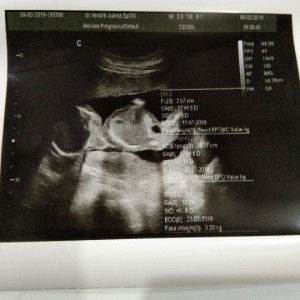

ada gak Bu hamil perutnya sedangan lah gak gede gak kecil jg to koq payudara Makin besar yah apakah itu wajar Bun?

Aku juga gitu bun, perut gg kliatan klo hamil 24 minggu, malah payudara yg gede

aq di usia kehamilah 21, perut ga begitu besar, malah PD nya yg besar